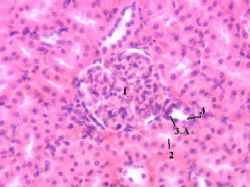

| 1,ж. Препарат - почка. Окраска гематоксилин-эозином. |

На этом снимке мы видим почечное тельце (1), проксимальные канальцы нефрона (2), дистальный каналец нефрона (3) и в нем - скопление клеток - плотное пятно (3.А). | Полный размер |